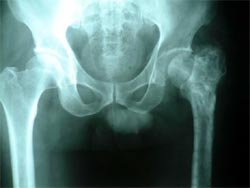

病例三

患者女性,45岁,左髋关节先天性脱位,股骨头坏死,疼痛明显,活动受限。采用生物固定全髋关节置换术,

髋臼予以加深没有植骨。术后5年复查,假体没有松动,关节功能良好,没有疼痛。